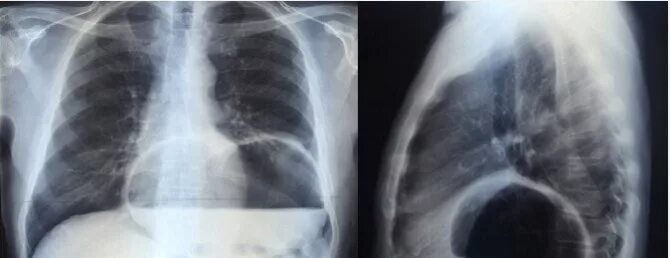

Ущемление грыжи диафрагмы